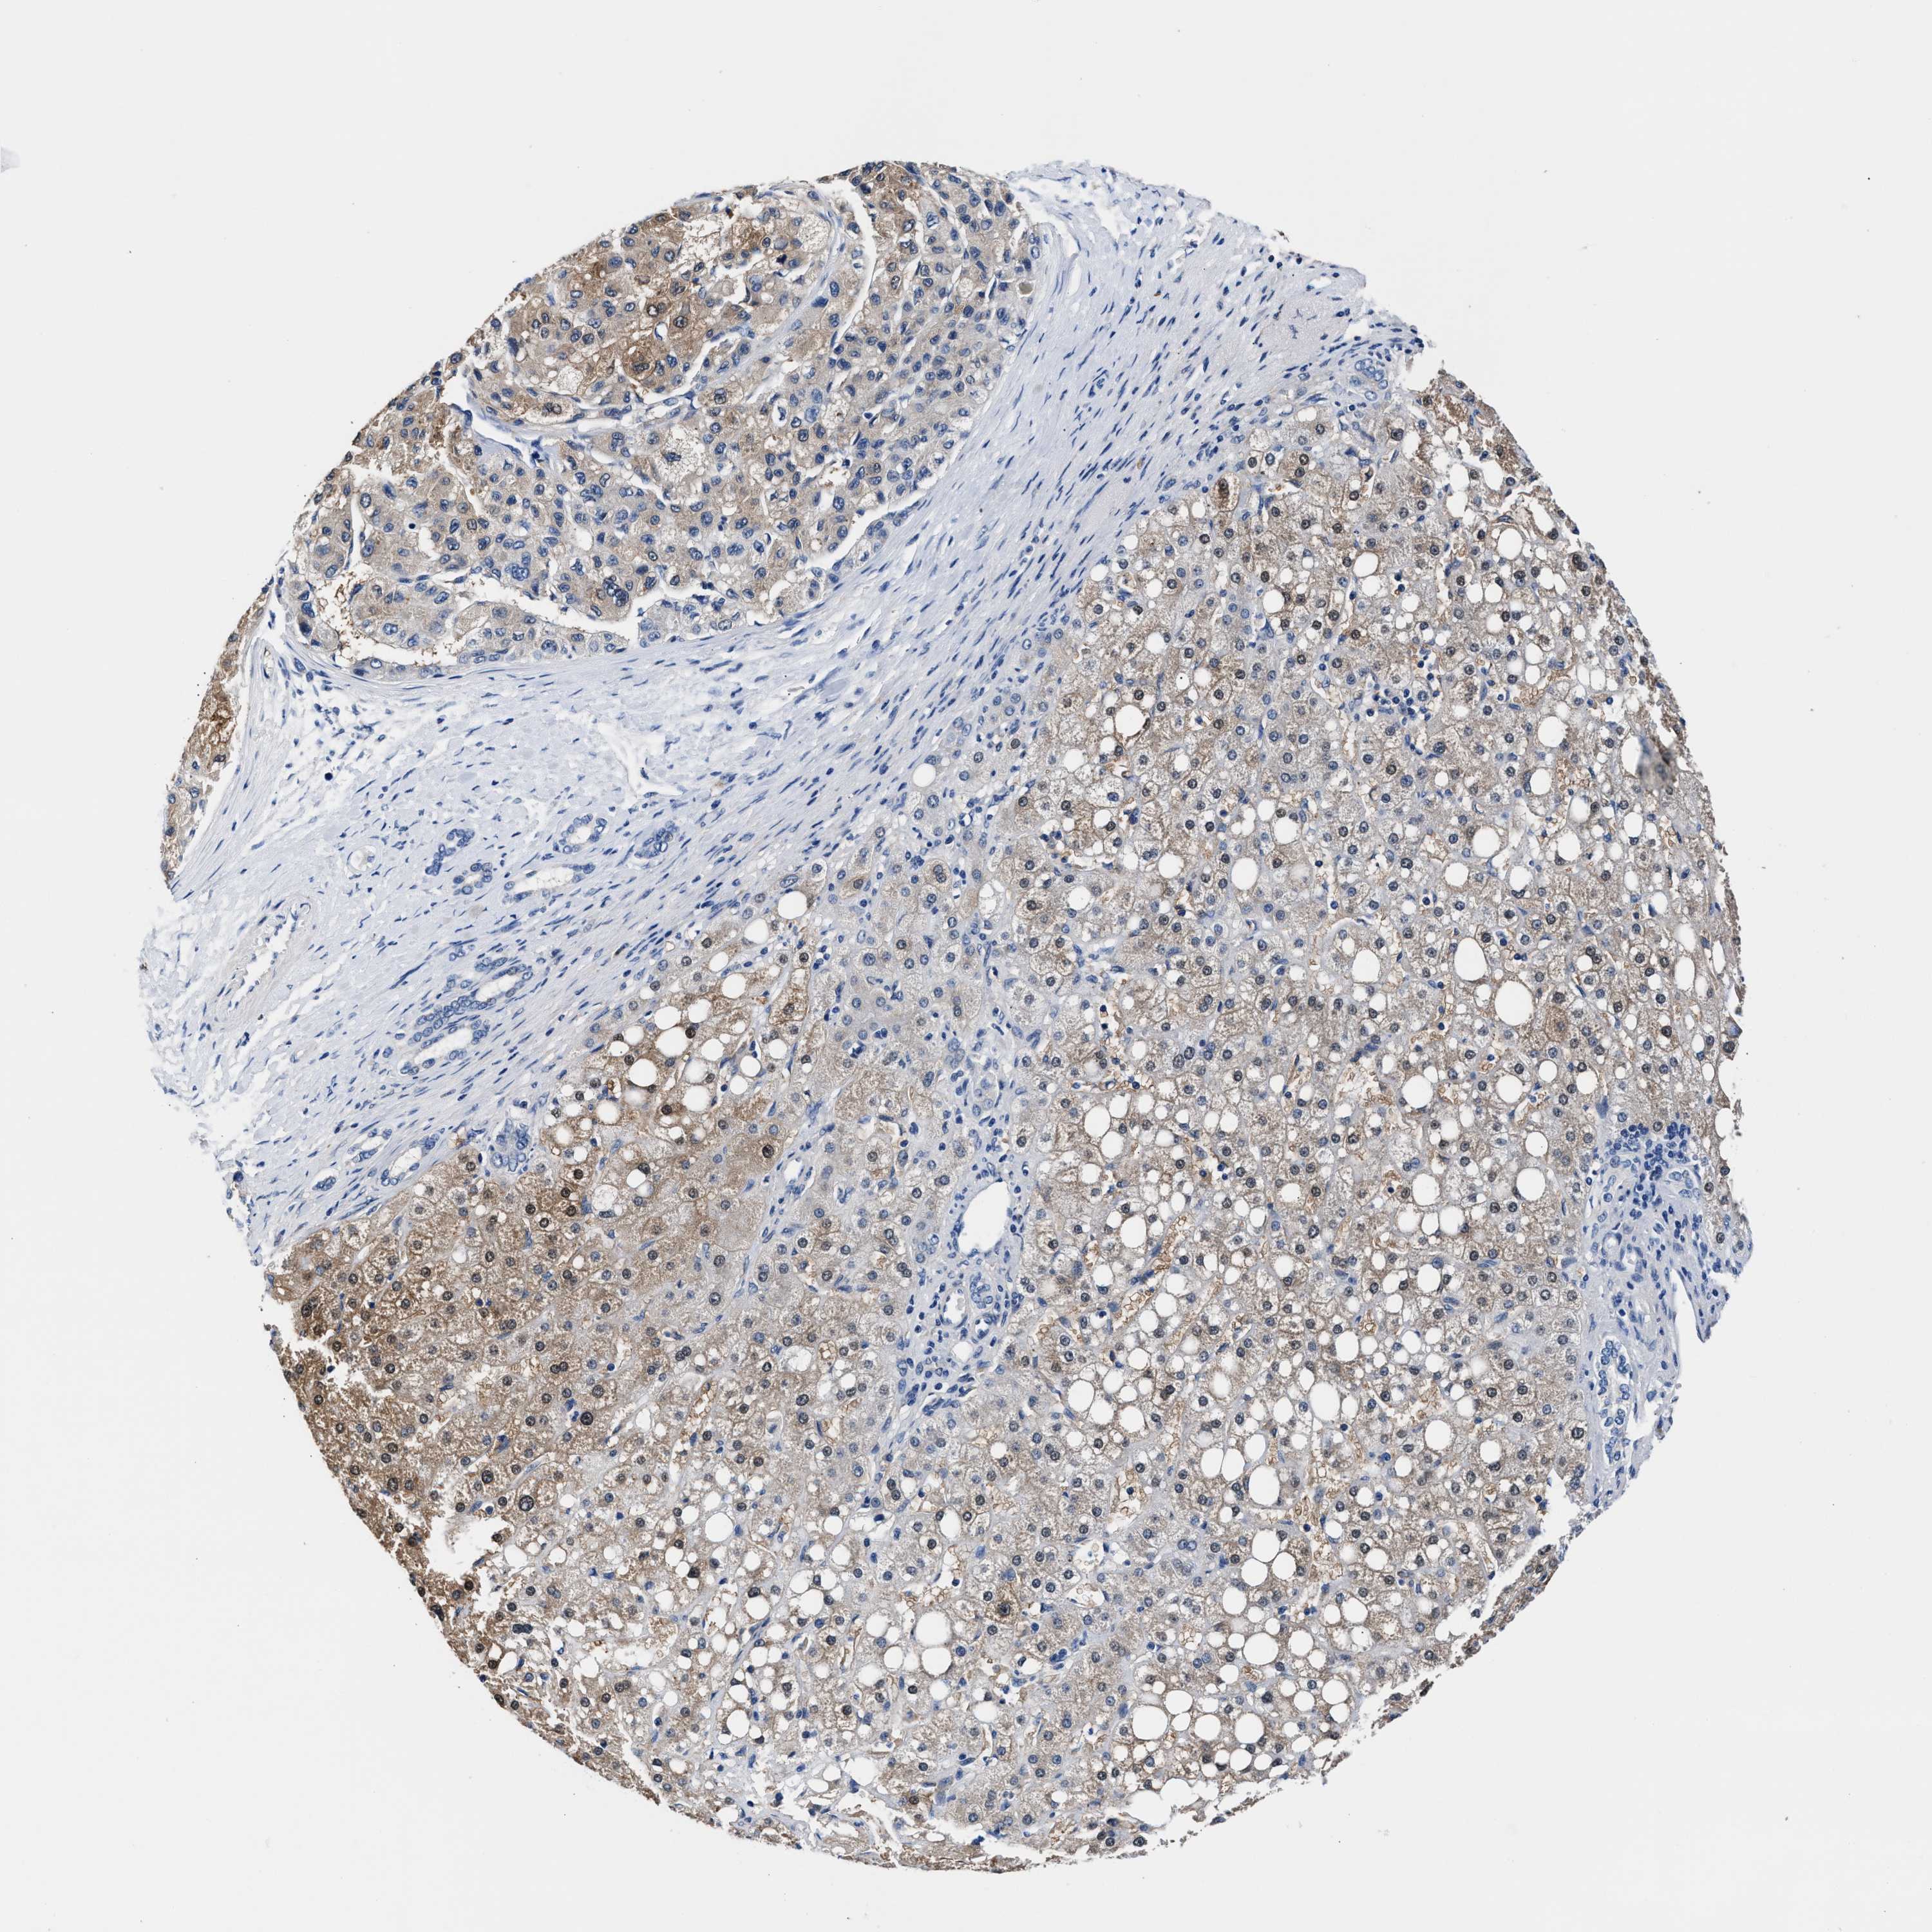

LIVER CANCER - Protein expressioni

A mouse-over function shows sample information and annotation data. Click on an image to view it in a full screen mode. Samples can be filtered based on level of antibody staining by selecting one or several of the following categories: high, medium, low and not detected. The assay and annotation is described here.

Note that samples used for immunohistochemistry by the Human Protein Atlas do not correspond to samples in the TCGA dataset.

Antibody stainingi

Antibody staining in the annotated cell types in the current human tissue is reported as not detected, low, medium, or high, based on conventional immunohistochemistry profiling in selected tissues. This score is based on the combination of the staining intensity and fraction of stained cells.

Each image is clickable and will lead to virtual microscopy that enables deeper exploration of all samples and also displays staining intensity scores, fraction scores and subcellular localization as well as patient and tissue information for each sample.

HPA048652

HPA055972

HPA055973

CAB022669

CAB047357

Staining

High

Medium

Low

Not detected

Intensity

Strong

Moderate

Weak

Negative

Quantity

>75%

75%-25%

<25%

None

Location

Nuclear

Cytoplasmic/membranous

Cytoplasmic/membranous,nuclear

Cholangiocarcinoma

Carcinoma, Hepatocellular, NOS